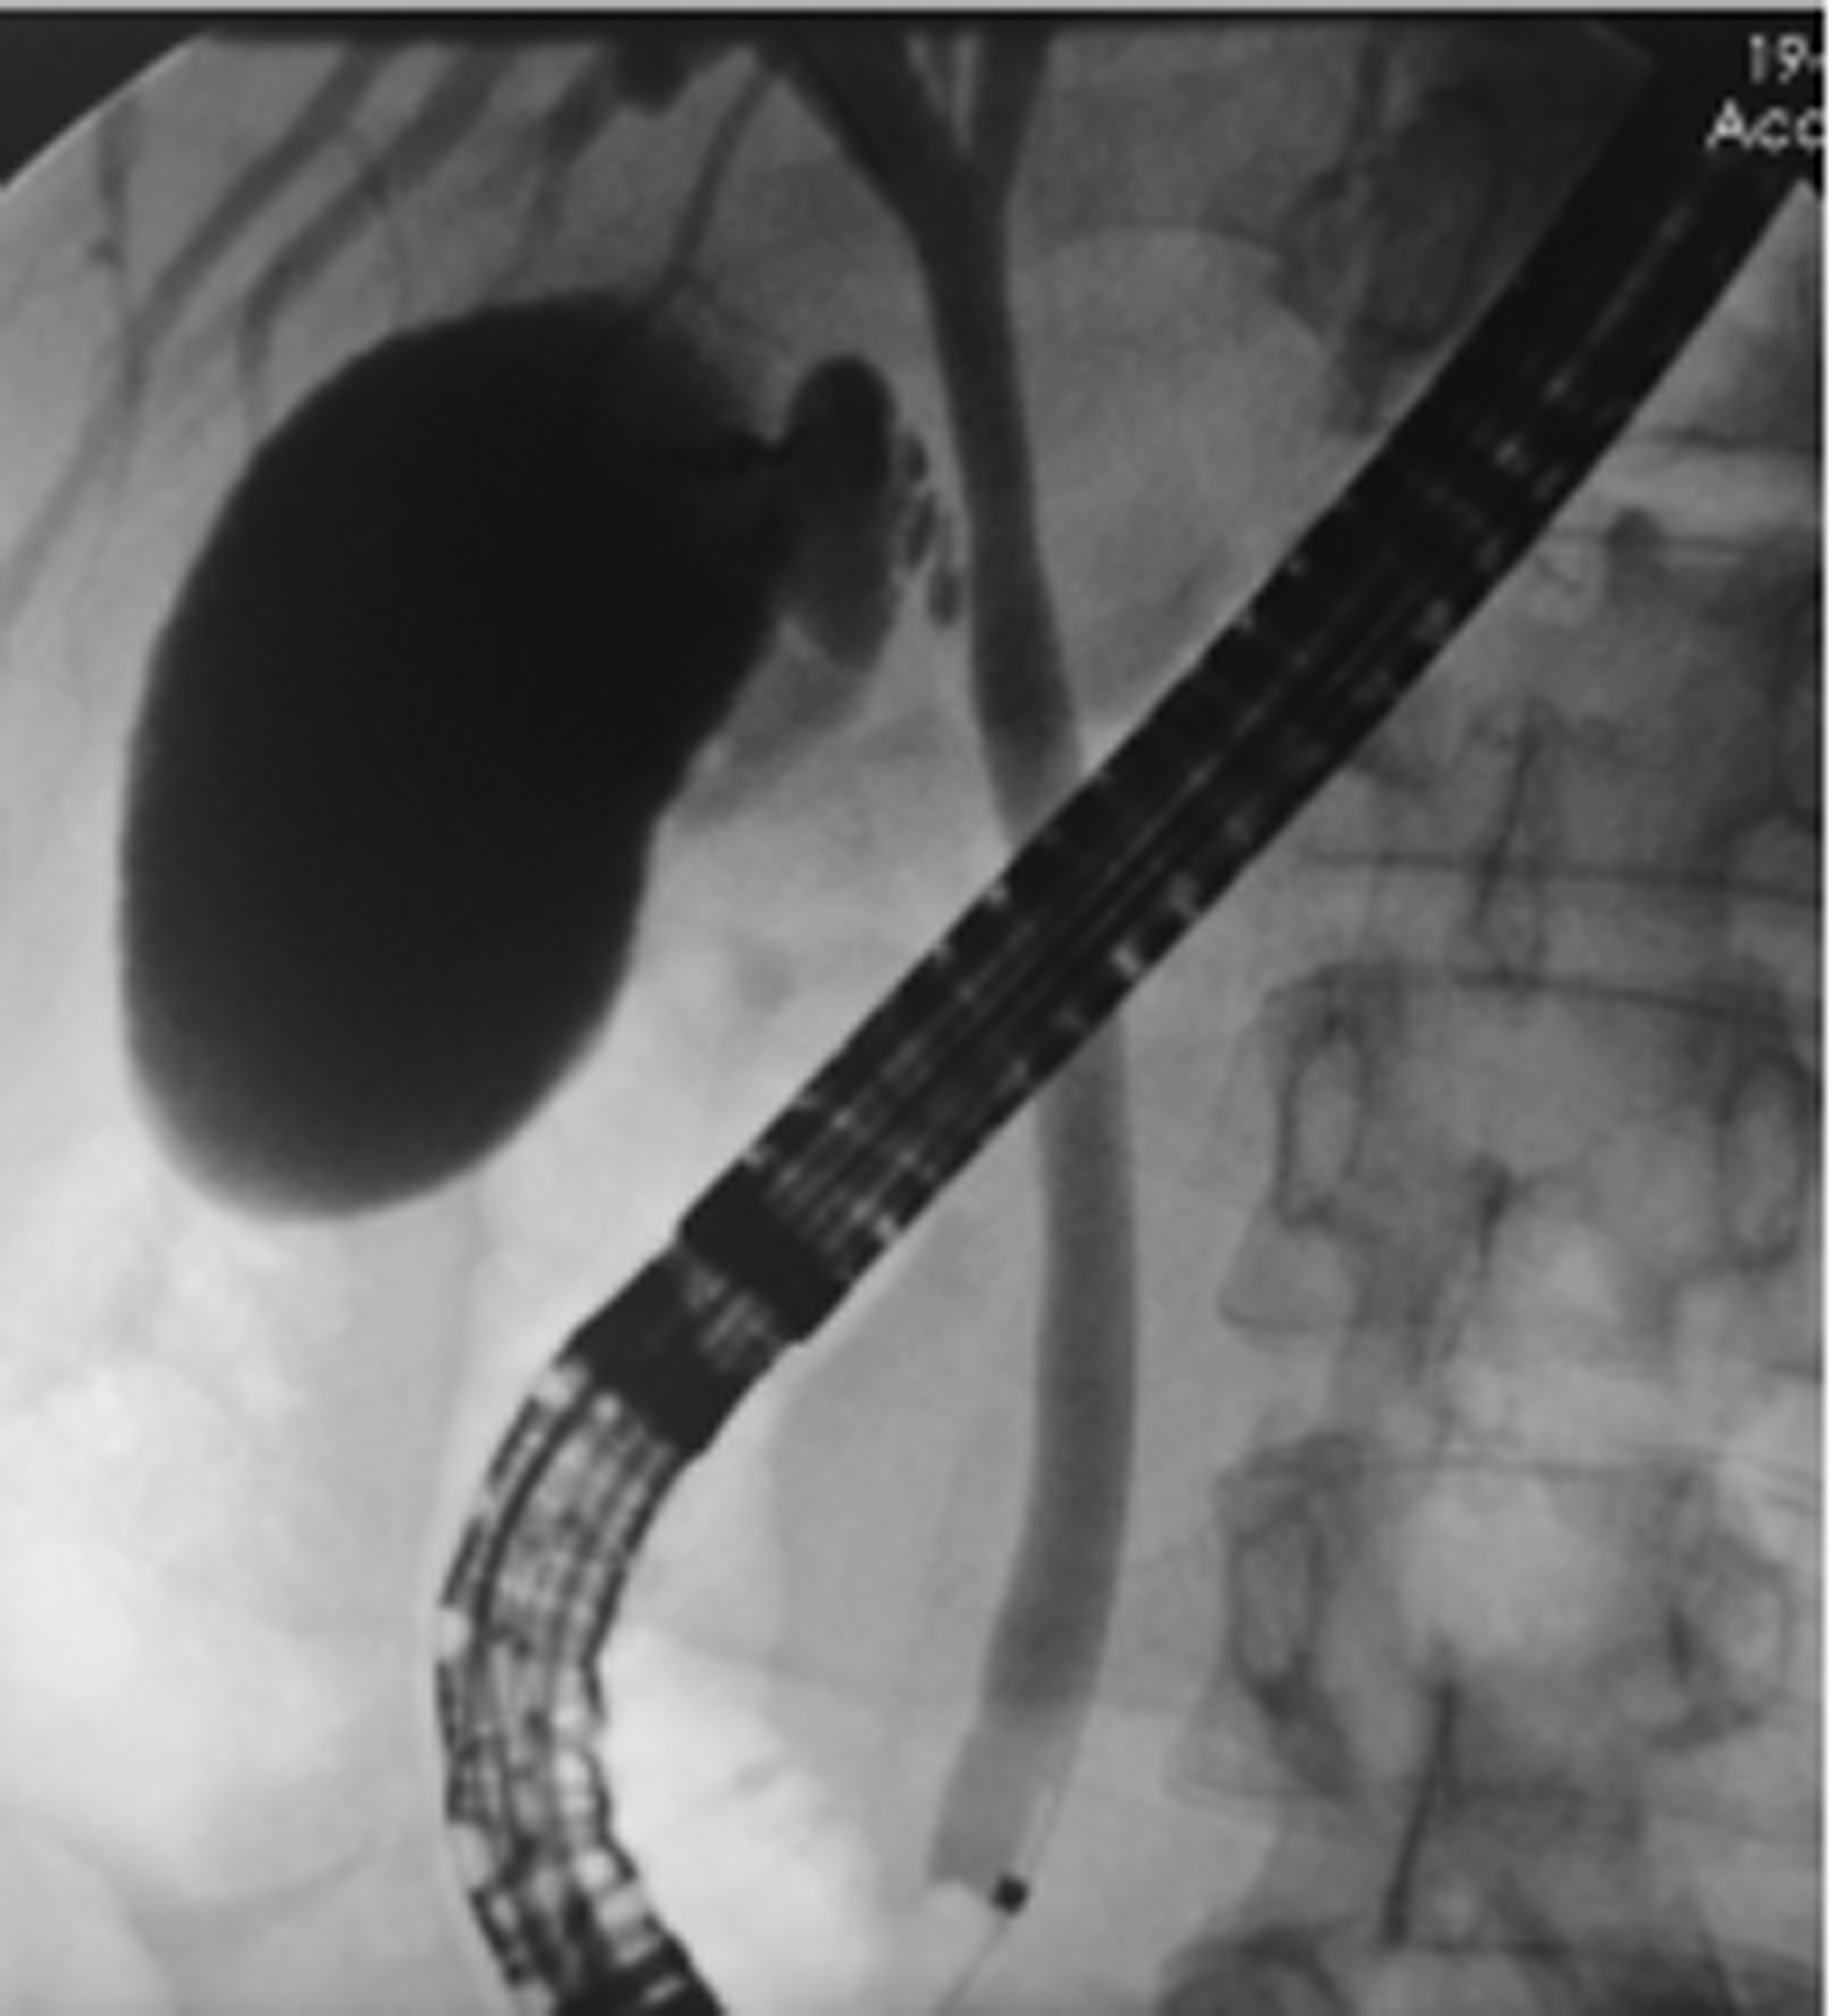

Selection of treatment regimens for pancreatic duct stones: A comparative analysis

Jinbin DONG, Weibing FANG, Yihai SHI

2022, 38(11): 2558-2564. DOI: 10.3969/j.issn.1001-5256.2022.11.023

Abstract(839) HTML (936) PDF (2050KB)(88)

Abstract:

Objective  To investigate the clinical efficacy of endoscopic retrograde cholangiopancreatography (ERCP), laparoscopy, and laparotomy in the treatment of pancreatic duct stones (PDS) by collecting related clinical data, to summarize the experience in selecting treatment regimens for PDS, and to further explore feasible treatment regimens that could maximize and optimize the benefits of PDS patients.  Methods  A retrospective analysis was performed for the clinical data of 131 PDS patients who were treated in Gongli Hospital Affiliated to Naval Medical University from June 2014 to December 2018, and according to the surgical procedure, they were divided into ERCP group with 69 patients, laparoscopy group with 32 patients, and laparotomy group with 30 patients. Related indices were monitored before and after treatment, and surgical outcome was compared between the laparoscopy group and the laparotomy group. The independent samples t-test was used for comparison of normally distributed continuous data between two groups; a one-way analysis of variance was used for comparison between multiple groups, and the least significant difference t-test or the SNK-q test was used for further comparison between two groups. The Mann-Whitney U test was used for comparison of continuous data with skewed distribution between two groups, and the Kruskal-Wallis H test was used for comparison between multiple groups. An repeated measures analysis of variance and the Friedman test were used for comparison of related indices before and after surgery, and the chi-square test was used for comparison of categorical data between groups.  Results  Among the 131 PDS patients, there were 40 patients with type Ⅰ PDS, 76 with type Ⅱ PDS, and 15 with type Ⅲ PDS. There was no significant difference in the distribution of main surgical methods between the laparoscopy group and the laparotomy group (χ2=1.93, P > 0.05). There were significant differences between the laparoscopy group and the laparotomy group in the dynamic changes of white blood cell count, C-reactive protein, procalcitonin, and Homeostasis Model Assessment of Insulin Resistance after surgery (F=24.68, χ2=227.66, F=45.37, F=106.71, all P < 0.05). Compared with the laparotomy group, the laparoscopy group had significantly shorter time of operation, significantly lower intraoperative blood loss, significantly shorter time to first flatus after surgery, a significantly lower frequency of use of pain-relieving drugs, shorter time to extraction of abdominal drainage tube, lower incidence rates of short-term postoperative complications, and a significantly shorter length of postoperative hospital stay (t=-4.80, t=-9.43, Z=-6.78, t=-11.59, Z=-6.77, χ2=9.24, t=-3.60, all P < 0.05). The incidence rate of short-term postoperative complications was 24.64% in the ERCP group, 28.13% in the laparoscopy group, and 66.67% in the laparotomy group, with a significant difference between groups (χ2=17.12, P < 0.05), and the ERCP group and the laparoscopy group had a significantly lower incidence rate of short-term postoperative complications than the laparotomy group (χ2=15.78 and 9.24, P < 0.05 and P=0.02). The treatment response rate was 91.30% in the ERCP group, 93.75% in the laparoscopy group, and 73.33% in the laparotomy group, with a significant difference between the three groups (χ2=7.70, P=0.02), and the ERCP group and the laparoscopy group had a significantly better response rate than the laparotomy group (χ2=5.56 and 4.77, P=0.02 and 0.03).  Conclusion  ERCP is the preferred method for minimally invasive treatment of some patients with type Ⅰ/Ⅱ PDS and is safe and effective with few serious complications. Surgical operation is an important method for the treatment of complex PDS, but with complicated techniques and difficult operation. Compared with laparotomy, laparoscopy has the advantages of small trauma, few serious complications, and high abdominal pain remission rate and can significantly shorten the time of operation, reduce intraoperative blood loss, and shorten the length of postoperative hospital stay. Therefore, laparoscopy should be the preferred regimen for the treatment of complex PDS.